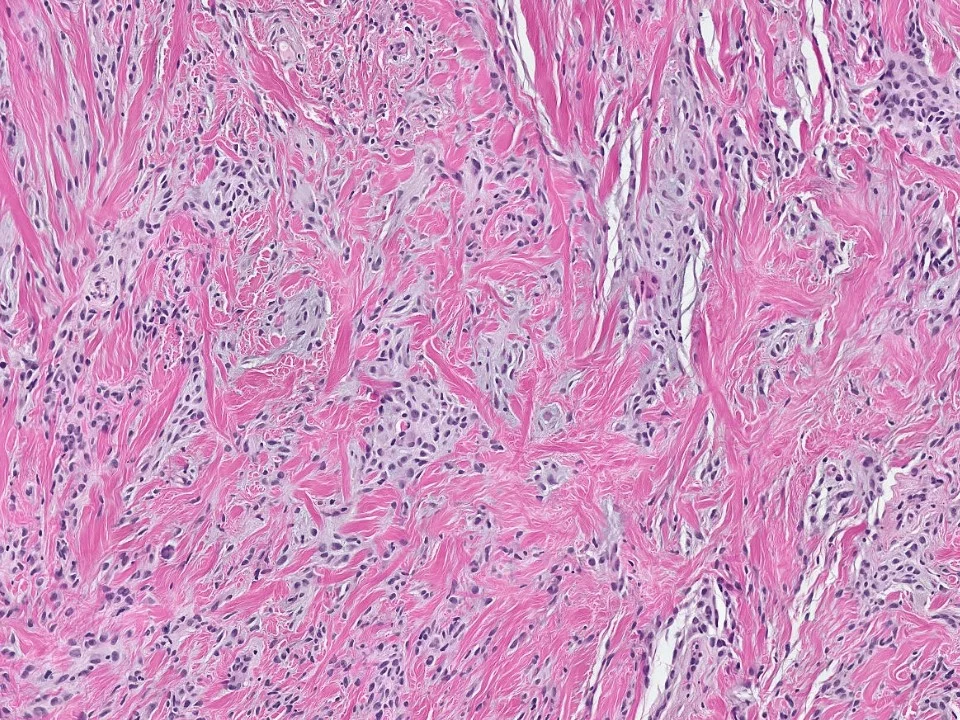

Fibromatosis

mammary fibromatosis is an infiltrative, locally aggressive proliferation of fibroblasts and myofibroblasts.

Histologically, mammary type fibromatosis is similar to desmoid-type fibromatosis in other sites. It is composed of uniform, bland spindle cells with pale eosinophilic cytoplasm, poorly defined cell borders, and oval to elongated and tapering nuclei. These cells can be seen infiltrating the stroma in long sweeping fascicles. Mitotic figures are usually not frequent. These lesions stain for beta-catenin.